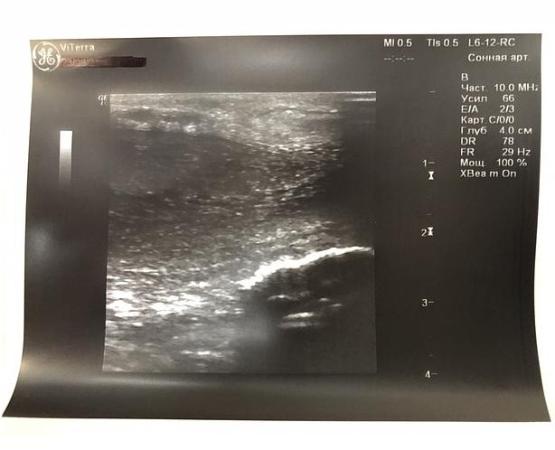

При УЗИ полового члена: белочная оболочка локально утолщена до 3,6 мм (норма - до 2мм).

По дорсальной поверхности полового члена ближе к его головке определяется гиперэхогенная тень размерами 0,48х0,04см (фиброзная бляшка), дающая чёткую эхо-тень в виде акустической дорожки.